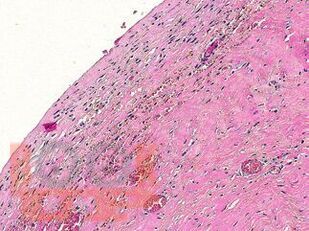

В атласе подробно изложено цитологическое и гистологическое описание всего спектра патологических изменений ткани молочной железы: неопухолевые, пролиферативные процессы, предраковые поражения, доброкачественные и злокачественные опухоли. Кратко представлены данные об этиологии, о патогенезе, молекулярной генетике, клинической картине и лучевых методах исследования различных поражений молочной железы. Подробно описаны дифференциальная диагностика и возможные ошибки морфологической диагностики. Атлас иллюстрирован большим количеством микрофотографий.